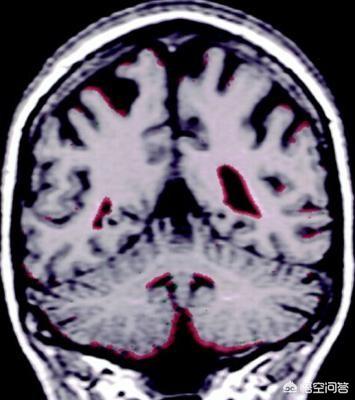

L'atrophie cérébrale, comme son nom l'indique, est un type de maladie mentale dans laquelle le cerveau rétrécit en raison de lésions organiques dans le cerveau pour diverses raisons. L'atrophie cérébrale survient chez les personnes âgées. Par exemple, nous connaissons la maladie d'Alzheimer, qui est une sorte d'atrophie cérébrale. Cette maladie se manifeste lentement et s'accompagne de pertes de mémoire, de changements de personnalité, de troubles du comportement et d'autres manifestations, et dans certains cas, de maux de tête, de vertiges, d'insomnie, de troubles de la mémoire, d'engourdissement des mains et des pieds et d'autres symptômes bénins. Les femmes dans la cinquantaine et la soixantaine présentent un risque élevé d'atrophie cérébrale, car le ralentissement de la circulation et de la vitesse du sang dans l'organisme entraîne une irrigation sanguine insuffisante de certains organes, ce qui est propice aux lésions. L'atrophie cérébrale est liée à l'hérédité, au niveau de vie et à des facteurs psychologiques.

L'atrophie cérébrale, c'est-à-dire un phénomène dans lequel le tissu cérébral lui-même subit des lésions organiques pour diverses raisons et produit une atrophie, n'est que le symptôme d'une maladie. L'hérédité, les traumatismes cérébraux, l'empoisonnement, les malformations vasculaires cérébrales, les tumeurs cérébrales, l'artériosclérose cérébrale, etc., toute maladie susceptible de modifier la circulation sanguine du cerveau et d'entraîner une ischémie chronique à long terme des tissus cérébraux, peuvent conduire à une atrophie cérébrale. Pour l'atrophie cérébrale, outre le traitement médicamenteux actif, la régulation du régime alimentaire est également très importante, comme le dit le proverbe : "trois parties de traitement et sept parties d'alimentation". Qu'est-ce qui est bon pour l'atrophie cérébrale ?